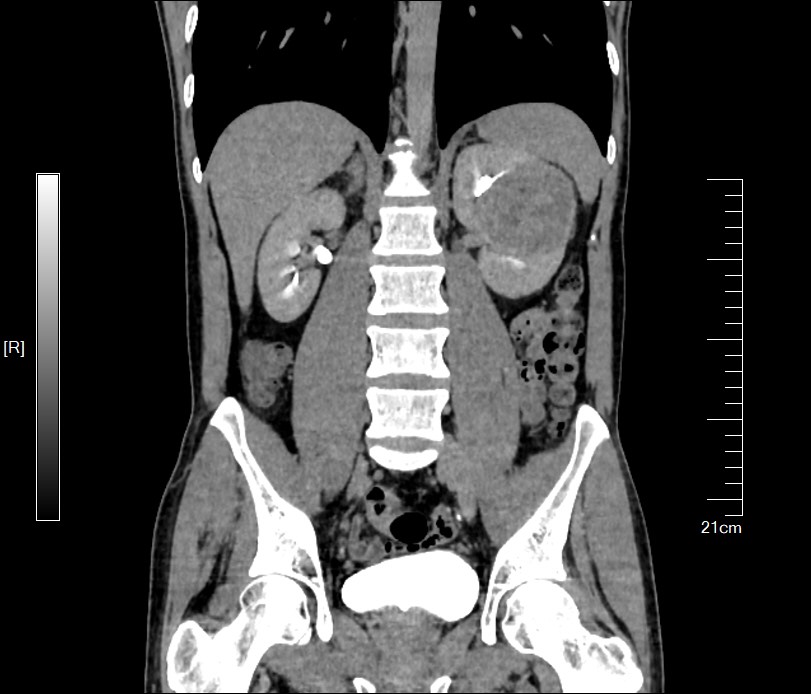

周先生住院进行了CT检查,发现在左侧肾脏上长了一个巨大的肿瘤,大约有7cm大小,占到了肾脏半数以上的体积。

手术后病理结果提示:(部分左肾)透明细胞肾细胞癌,WHO/ISUP:2级,切缘阴性。